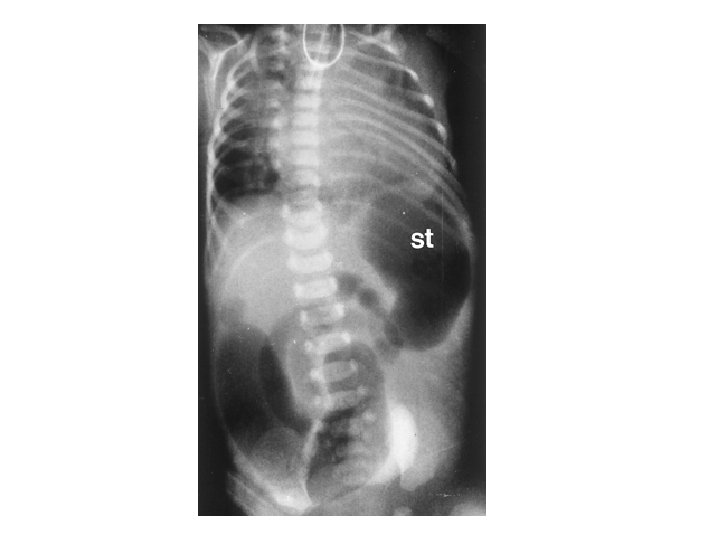

Case 2 Early Course • Trophic feeds re-started d 14 – Stopped on d 17 for abdominal distension – Prominent bowel loops, no pneumatosis – NPO for 7 days • Feeds re-started around d 21 • NPO again on 8/29 (d 30) for abdominal distension Jose Chavez CHO MR 960117

Case 2 Transfer • • • Transferred on 8/30 (1 month) for PDA ligation 800 g, systolic murmur, abdomen distended but soft NPO on HA PC/PS 17, PEEP 8, Rate 50 Multiple meds: – – – – Albuterol Pulmicort Caffeine Lasix Fluconazole Vancomycin Phenobarbitol Ativan Jose Chavez CHO MR 960117

Case 2 Radiology Evaluation • Upper GI – Flow through normal duodenum, duodenal-jejunal junction, jejunum • Contrast enema – Microcolon – Distended RUQ loops do not fill during enema • Small bowel follow-through – Opacification of distended loops Jose Chavez CHO MR 960117